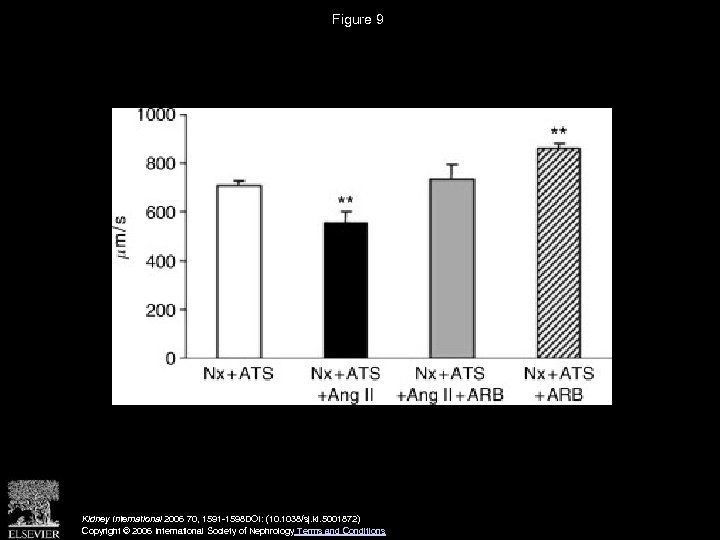

Figure 9 Kidney International 2006 70, 1591 -1598 DOI: (10. 1038/sj. ki. 5001872) Copyright © 2006 International Society of Nephrology Terms and Conditions